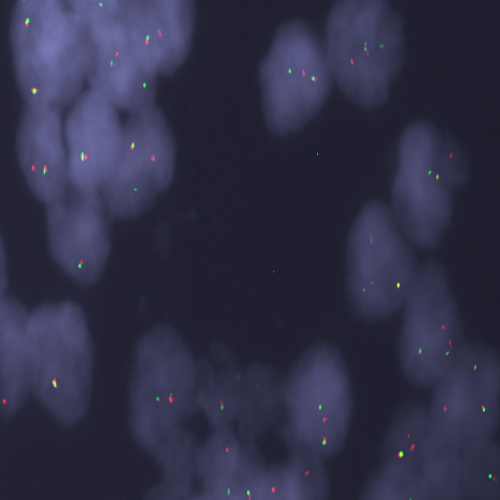

Human fibroadenoma (serial sections): immunohistochemical staining for Progesterone Receptor (A and B forms). Note a smaller proportion of weakly staining tumor cell nuclei in A compared to B. Progesterone Receptor (A/B Forms): clones 16/SAN27

Product Specific Information The cocktail has been formulated using two clones, clone 16, specific for PRA, and SAN27, specific for PRB.